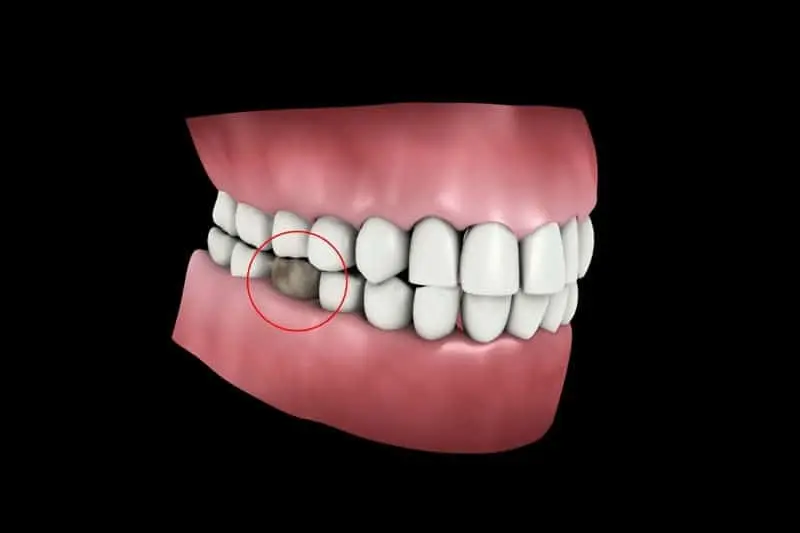

4. Ngăn Ngừa Xô Lệch Răng

– Răng số 5 giúp duy trì sự cân bằng và ổn định của toàn bộ cung hàm. Khi mất răng, các răng kế cận có xu hướng xô lệch vào khoảng trống, gây ra tình trạng răng khấp khểnh, sai khớp cắn.

2. Xô Lệch Răng

– Các răng kế cận (răng số 4 và răng số 6) sẽ có xu hướng nghiêng về phía khoảng trống, gây xáo trộn khớp cắn. Điều này dẫn đến tình trạng khó nhai, đau khớp thái dương hàm và tăng nguy cơ sâu răng do thức ăn dễ bị mắc kẹt.